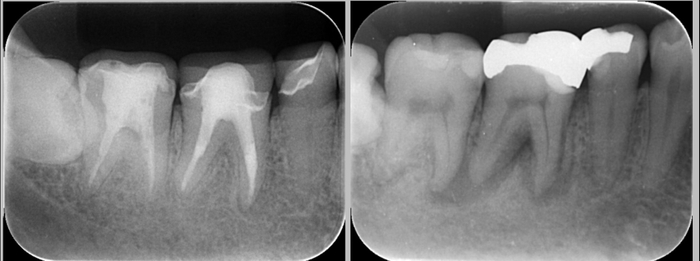

右が2015年ご来院時の治療前のレントゲン写真。黒く影になっているところが病変。左が2025年、一時帰国時の定期健診のレントゲン写真。溶けていた骨が再生されたために、根の先の黒い影が消失している。